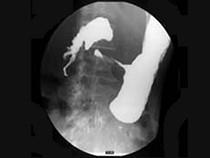

问题 女,56岁,上腹部钝痛、腹胀不适1月余,纳差、消瘦,影像检查如图,最可能的诊断是()

选项 A.胃幽门管溃疡 B.胃腺癌并幽门狭窄 C.胃淋巴瘤 D.胃间质瘤 E.胃恶性间质瘤

答案 B